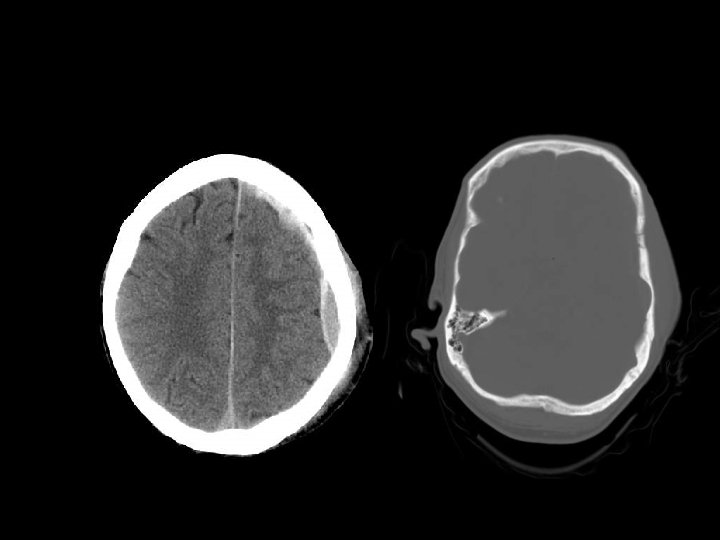

EXTERNAL HERNIATION n Akibat defek pada skull dengan kombinasi peningkatan tekanan intrakranial n Obstruksi vena dapat timbul pada tepi defek